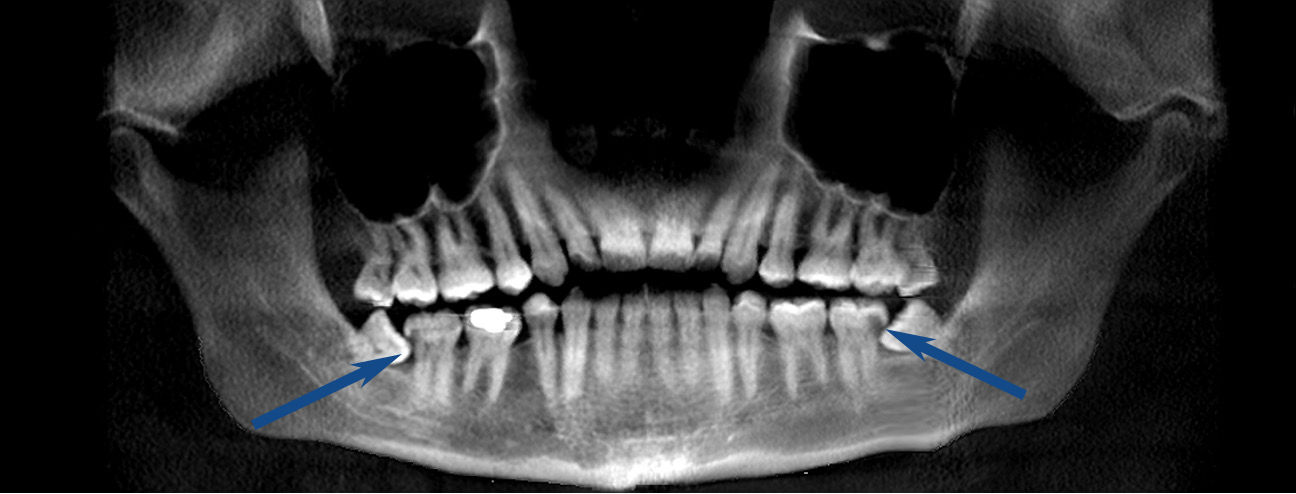

One lower wisdom tooth had tipped forward at nearly a 45-degree angle, wedging itself beneath the adjacent second molar. From another angle, the tooth appeared even more severely angled, closer to 60-80 degrees.

Eventually, the decay extended to the root surface of the second molar, as shown in the X-ray below.

Once decay reaches the root surface, the tooth often cannot be restored with a filling or crown. As a result, both the wisdom tooth and the otherwise healthy second molar had to be removed.

Two years after losing the first wisdom tooth and molar, he returned with the same problem on the opposite side. Despite earlier intervention, the decay had progressed there as well. He then required removal of the lower wisdom tooth and the adjacent second molar on that side.